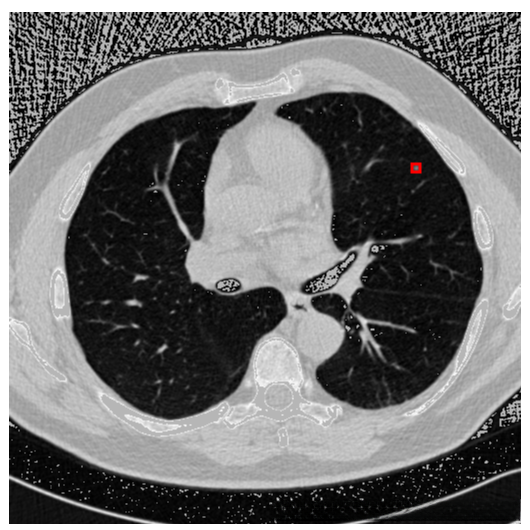

下图左边是预测,右边是根据标注生成的ground truth。

更新: 2019.9.23

修改anchor size后重新训练